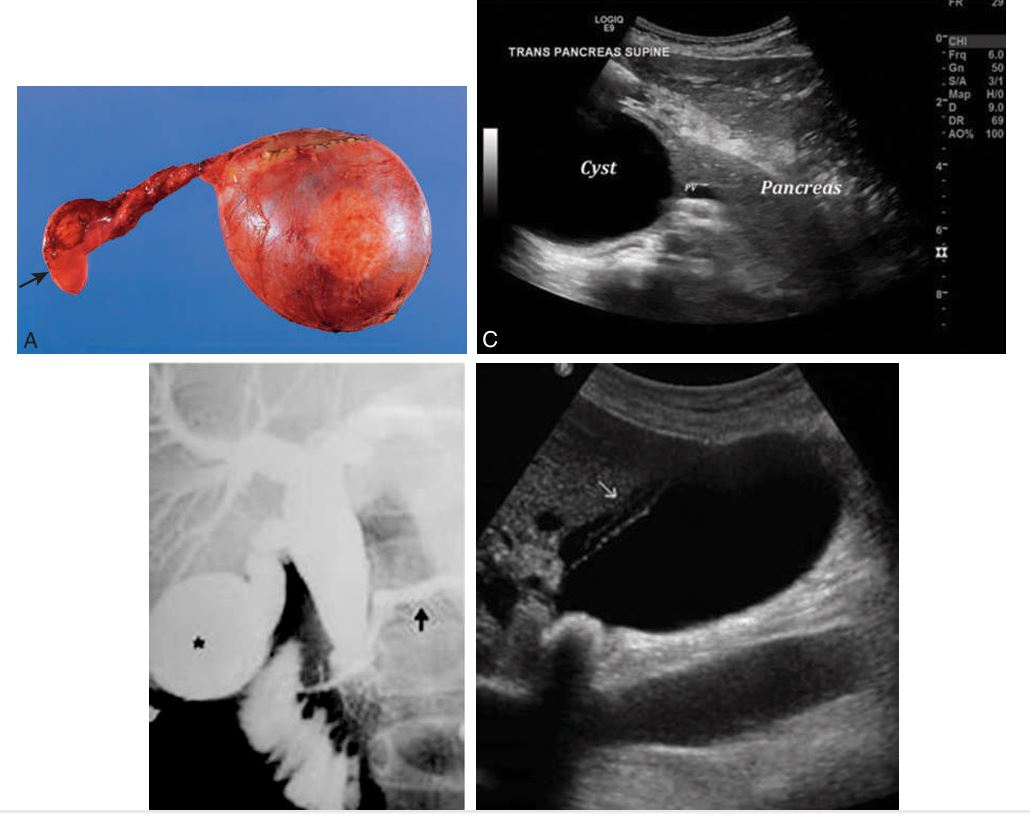

Choledochal Cyst

Rare, primarily congenital

More common in women than in men (4:1)

Higher incidence in infants than adults

linked with gallstones, pancreatitis, or cirrhosis, cholangitis

SymptomsAbdominal mass

Pain

Fever

Jaundice

increased BILIRUBIN

Diagnosis may be confirmed with a nuclear medicine hepatobiliary scan

Type I is a fusiform dilation of the common bile duct is Most common, along with type Iva

Choledochal Cysts

Rare congenital abnormality most likely inherited in an autosomal recessive fashion.

Communicating cavernous ectasia of the intrahepatic ducts characterized by congenital segmental saccular cystic dilation of major intrahepatic bile ducts.

Found in the young adult or pediatric population;

may be associated with renal disease or congenital hepatic fibrosis

symptoms

Recurrent cramplike upper abdominal pain, secondary to biliary stasis, ductal stones, cholangitis, and hepatic fibrosis.

Two types of Caroli’s disease

Simple classic form

More common form associated with periportal hepatic fibrosis

Caroli’s Disease (medullary sponge kidney) is strongly associated

Transverse and longitudinal scan of a young patient with a choledochal cyst (Ccy) in the right upper quadrant.

Localized cystic dilation of the common bile duct

Diverticulum from the common bile duct

Invagination of the common bile duct into the duodenum

Dilation of the entire common bile duct and the common hepatic duct

4 pics of Choledochal Cysts

what is this disease associated with…this is carolis disease

MEDULLARY SPONGE KIDNEY